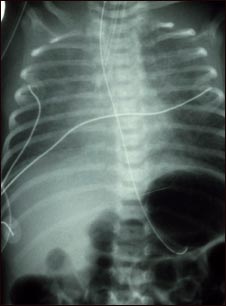

Retorno venoso pulmonar total anómalo, rayos X

El retorno venoso pulmonar anómalo total es un tipo de enfermedad cardíaca congénita. Esta radiografía muestra un aumento de tamaño del corazón, del hígado y de los vasos sanguíneos pulmonares (vascularidad pulmonar).